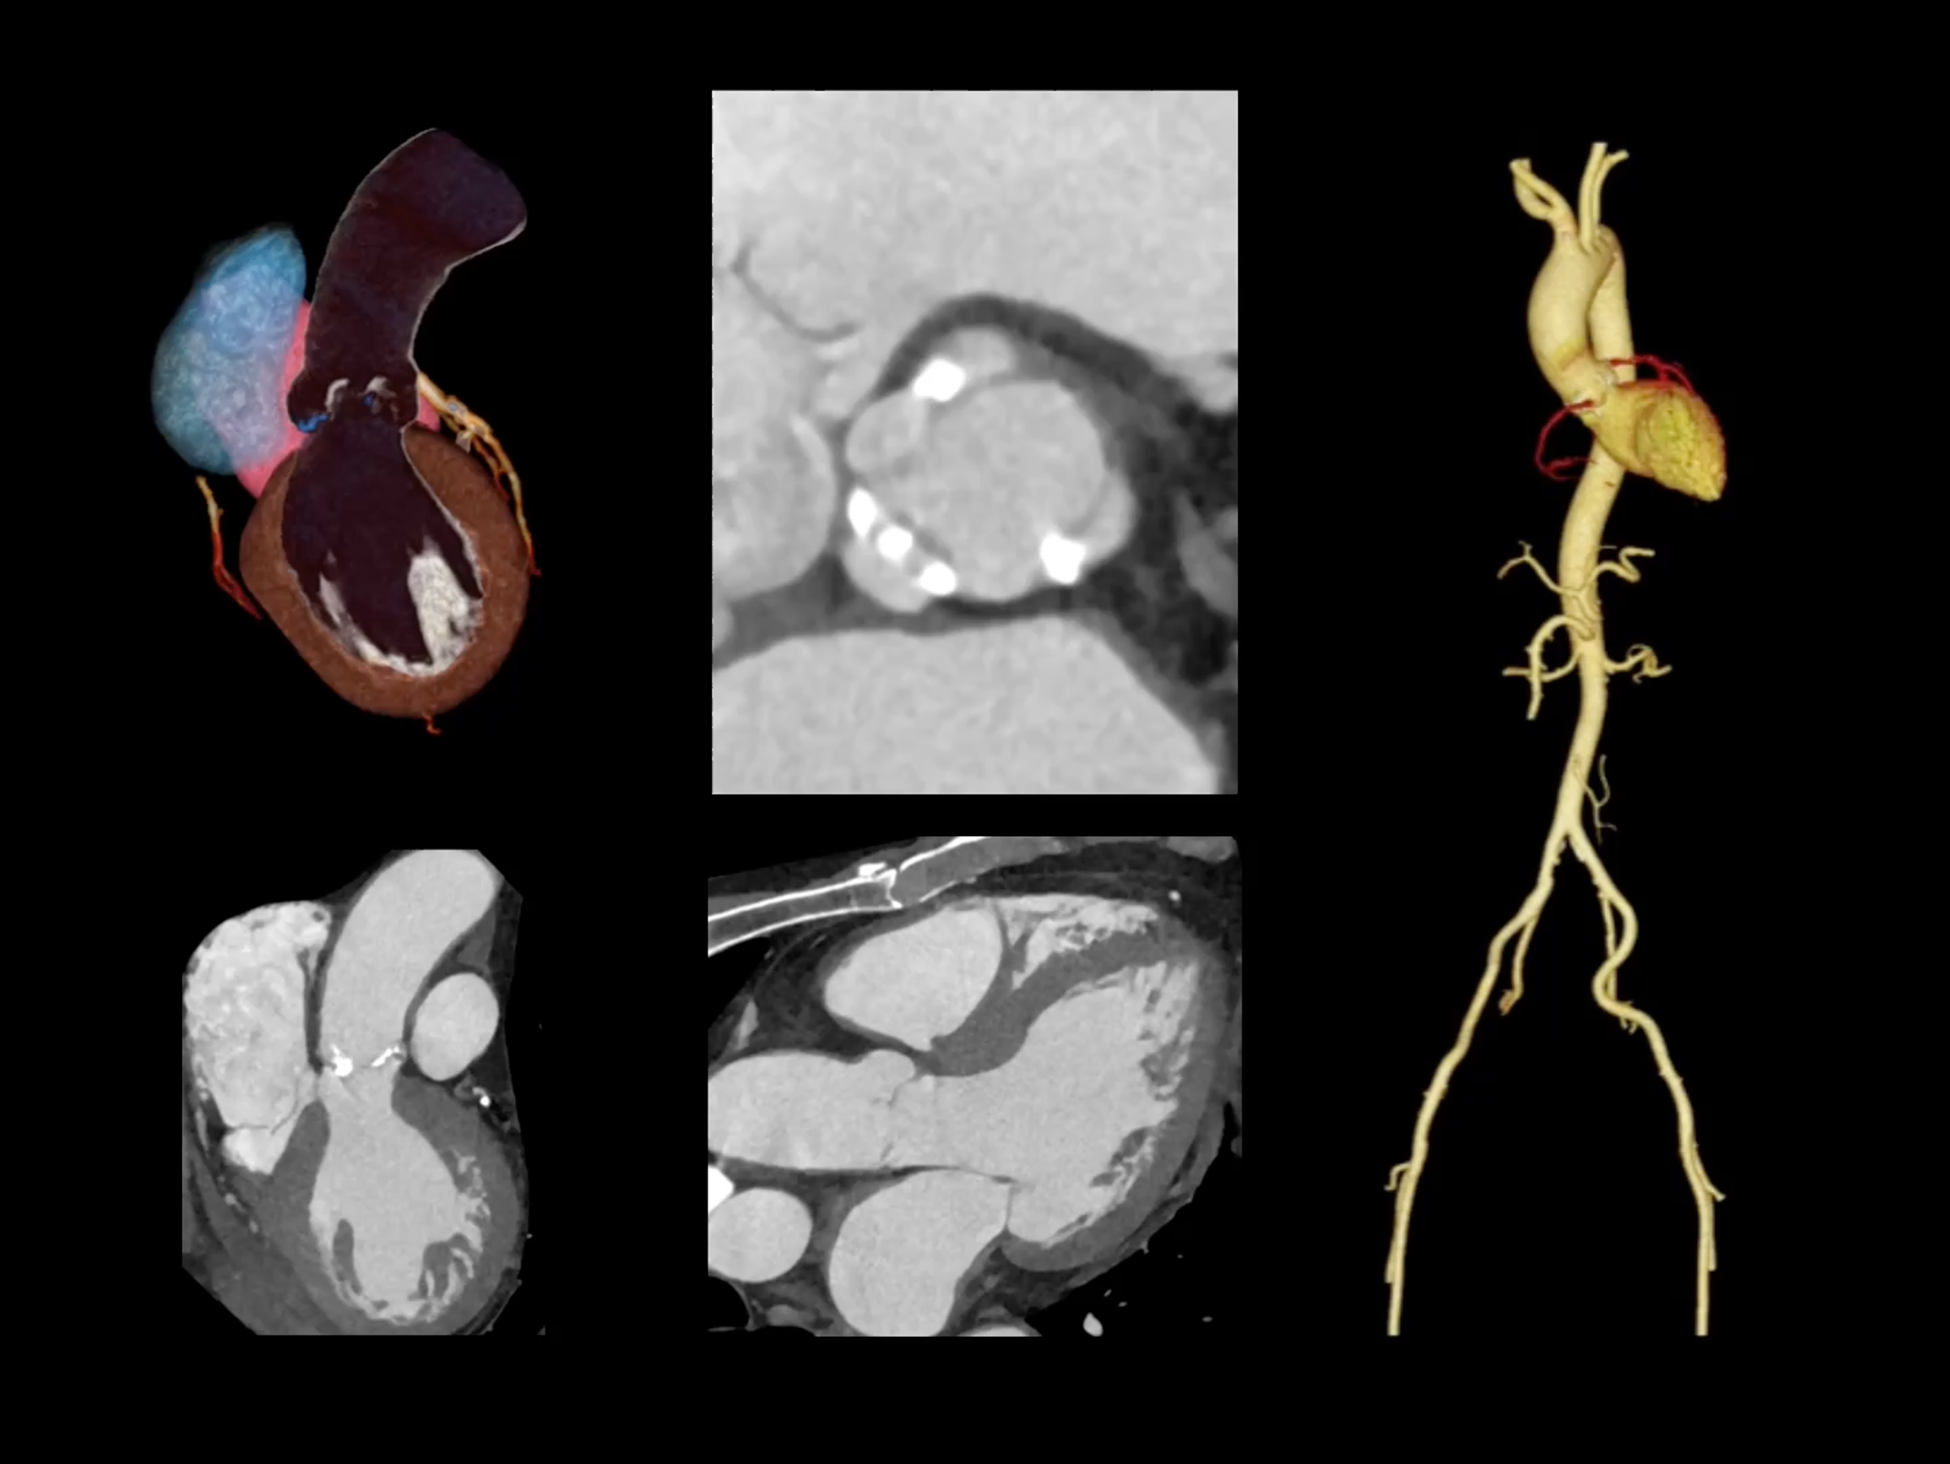

一站式心脏多维成像

一次对比剂注射可同时获取冠脉CTA、心肌灌注和心肌延迟强化等多维图像信息。

全域能谱

uCT SiriuX® 依托16cm超宽探测器与双源能谱技术,实现真正意义上的全身高清能谱成像。单次扫描同步获取灌注、能谱等多维定量参数,精准解析组织特性与病灶成分,为临床决策提供更深层次的诊断依据。

全身高清能谱成像

uCT SiriuX® 采用独有的双宽体探测器设计,实现470mm超大视野与全脏器容积覆盖的能谱成像,轻松应对不同体型患者和扫描部位应用需求。配合创新能谱重建影像链与精准双能数据配准,系统可有效抑制伪影、提升信噪比,在全脏器范围内提供高质量能谱图像,显著拓展临床精准诊断的广度与深度。

能谱成像可揭示丰富的物质与能量信息,其临床价值的充分释放有赖于完善高效的后处理分析平台。uCT SiriuX® 提供全面能谱高级分析工具,覆盖心血管、肿瘤、神经、骨科等多类临床场景。平台支持动脉增强分数分析(AEF)、细胞外容积分析(ECV)、肿瘤同源性分析、肺栓塞分析、骨髓水肿分析等多项评估,并提供多达10种基物质对成像,为精准诊断与科研探索提供坚实支撑。